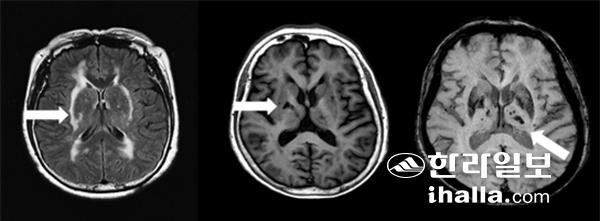

유전적인 원인으로 뇌졸중이 발생하는 대표적인 질환은 카다실(CADASIL)이라고 불리는 질환이며, 염색체 19번에 위치하는 노치3(NOTCH3) 유전자의 돌연변이로 인해 뇌의 작은 혈관에 손상이 발생하는 것이 특징이다. 카다실은 부모 중 한명이라도 질환이 있는 경우 자녀의 50%에서 질환이 발생하는 우성유전 양식을 보인다. 카다실의 주된 증상으로는 뇌졸중, 인지기능장애, 편두통, 정신과적 증상 등을 들 수 있다(그림 1).

뇌졸중은 카다실의 가장 흔하고도 중요한 증상으로 환자들의 2/3에서 관찰되며 일반적인 뇌졸중과 달리 40대부터 조기에 발생하고 재발이 흔하며 반복적인 뇌졸중으로 치매, 진행성 보행장애 등이 발생할 수 있다. 주로 작은 뇌동맥이 막혀서 발생하는 뇌경색이 흔하지만 일부 환자들은 뇌혈관의 파열에 의한 뇌출혈도 발생한다.

카다실의 진단은 주로 혈액검사를 통한 유전자 분석으로 이뤄지고 검사 후에 결과를 확인하는데 수 주의 시간이 필요하다. 또한 뇌자기공명영상검사(MRI)를 시행하는 경우 뇌백질에 고신호강도의 병변을 통한 진단이 이뤄진다. 질환이 진행될 수록 백질 고신호강도 병변의 수와 범위가 늘어나고 열공성 뇌경색, 뇌미세출혈, 뇌위축 소견 등이 나타난다. 뇌자기공명영상 소견은 환자들의 예후를 예측하는 데도 중요한 역할을 한다. 하지만 카다실 환자를 뇌자기공명영상소견 만으로 일반적인 뇌졸중과 구분하는 것은 한계가 있다(그림 2).

카다실은 비교적 드문 질환으로 환자-보호자 뿐 만 아니라 의사들도 이 질환에 대한 지식이 제한적이고 임상 증상, 뇌영상소견만으로는 일반적인 뇌졸중과의 구별이 쉽지가 않아서 질환이 의심되는 경우 유전자 진단이 필수적이다.